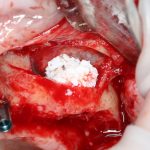

Изоляция области аутографта и имплантатов барьерной мембраной.

Перекрывать костный блок барьерной мембраной или оставить так? По этому вопросу есть много мнений. Между тем, в публикации по методике есть ясное показание, когда это требуется.

Конкретно в этом клиническом случае между костным аутотрансплантатом, ложем и имплантатами есть пустое пространство. Если его не изолировать от мягких тканей, они прорастут и осложнят интеграцию аутографта. Поэтому я решил перекрыть костный блок барьерной мембраной, пусть это делает хирургическую операцию немного дороже.

На этом этапе есть несколько нюансов, о которых я хочу рассказать отдельно.

— я использовал барьерную мембрану Geistlich Bio-Gide, которая имеет две разные поверхности: с одной стороны она рыхлая «адгезивная», с другой — гладкая и прочная. Как укладывать — на результат не влияет, но в плане удобства рыхлую поверхность мы «приклеиваем» к тому, на чем требуется барьерную мембрану удержать. В данном случае хотелось бы удержать её на костной поверхности — следовательно, мы укладываем её рыхлой поверхностью к кости.

— много лет мы используем антибиотики для интраоперационной профилактики инфекционно-воспалительных осложнений. Уже в то время мы пришли к выводу, что удобнее всего — порошки антибактериальных препаратов для приготовления раствором: дешевые, стерильные, в удобной упаковке. Прямо в виде порошка их можно добавлять в графт, растворы для ирригации, либо использовать так, как показано на фото. Еще мы используем порошок антибиотика для изготовления пасты, которой обрабатываем имплантаты в процессе ревизии или при лечении периимплантита. Это удобнее и эффективнее, чем интраоперационное использование жидких форм антибактериальных препаратов.

— ты знаешь, что барьерная мембрана может выполнять две функции, каркасную и изолирующую. Первая функция требует обязательной фиксации и натяжения, вторая — нет. В нашем случае «каркасом» регенерата является костный блок, а барьерная мембрана нужна только для изоляции. Поэтому она не требует натяжения и фиксации пинами.

После я внимательно проверил, что костный блок и имплантаты полностью перекрыты. Теперь рану можно ушивать.